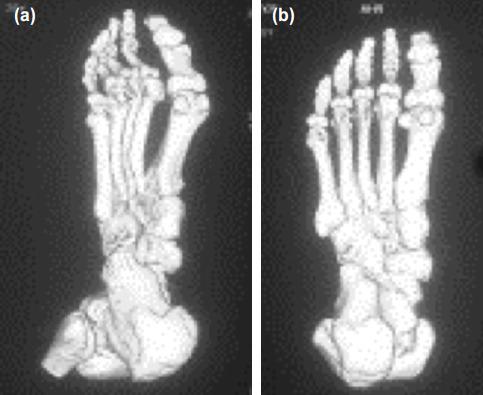

Twenty patients with Freiburg's infraction were admitted at our hospital over a period of six years. Patients with a normal plantar contour of the metatarsal head were included. All patients underwent a dorsal closing wedge osteotomy of the metatarsal.

六年间,我院收治了20例弗赖贝格骨折患者。纳入跖骨头足底轮廓正常的患者。所有患者均接受了跖骨背侧闭合楔形截骨术。